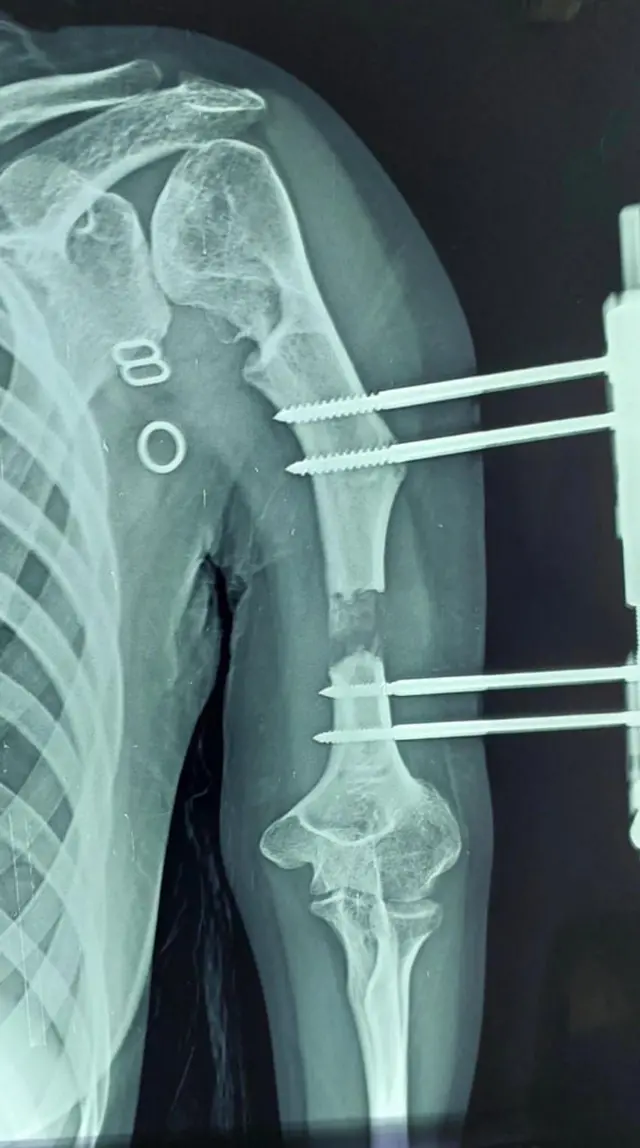

"ஒருவரின் வளர்ச்சி குறைபாட்டுடன் கூடிய எலும்பை அறிவியல் ரீதியாக செயற்கையாக முதலில் உடைப்போம். பின்னர் ஒரு வெளிப்புற கருவியை (external fixator) நோயாளியின் எலும்புடன் பொருத்தி தையல் போடப்படும். இந்த கருவி நோயாளியின் தோலுக்கு வெளியேதான் இருக்கும். அந்த கருவியை ஒவ்வொரு நாளும் சுழற்றும்போது, எலும்பு ஒரு சவ்வு போன்று நீட்சியடையும். சுவிங்கத்தை மென்று அதை இழுத்தால் எப்படி நீளுமோ அதுபோன்ற நெகிழ்வுத்தன்மை எலும்புக்கு உள்ளது." என்கிறார் மருத்துவர் சுரேஷ்.

இந்த அறுவை சிகிச்சை முடிந்து பத்து நாட்களுக்குப் பிறகு, அந்த வெளிப்புற கருவியில் உள்ள திருகு போன்ற அமைப்பை திருகுவதன் மூலம் எலும்பு சவ்வு போன்று நீட்சியடைகிறது.

அதாவது, நாளொன்றுக்கு ஆறுமணி நேரத்துக்கு ஒருமுறை அந்த கருவியின் திருகு போன்ற அமைப்பை சுழற்றும்போது, உள்ளே உள்ள எலும்பு கீழே இழுக்கப்பட்டு வளர்கிறது. இந்த அமைப்பை திருகுவதை நோயாளிகளே செய்யும் அளவுக்கு எளிமையான செயல்முறையாக உள்ளது.

distraction osteogenesis எனும் சிகிச்சை முறையில் இது மேற்கொள்ளப்படுகிறது. இந்த சிகிச்சை முறையில் ஒருநாளைக்கு ஒரு மி.மீ என்ற அளவில் எலும்பு சவ்வு போன்று நீளும், அப்படியென்றால் ஒரு செ.மீ வளர பத்து நாட்களாகும்.